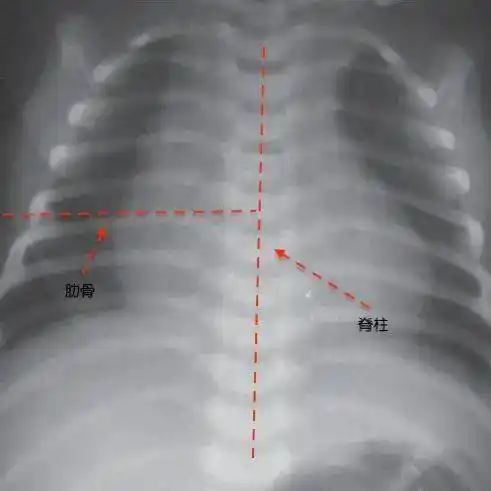

宝宝肋骨外翻就是佝偻病?